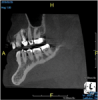

(4.) In a CBCT image axial view, the MB1 and MB2 canals are readily visible in tooth No. 14, and in the coronal view, these two separate canals can be seen to merge into a single apical opening.

Figure 4

Being able to see the number and shape of the canals accurately prior to treatment is the desire of any clinician who performs endodontics. Research suggests that, due to improved diagnostic accuracy, the final treatment plan may change in up to 50% of endodontic cases if CBCT is used rather than traditional 2D imaging.14,15 The question of whether or not a patient has an MB2 canal can be answered prior to opening the access preparation (Figure 4 and Figure 5). Visualizing single canals that bifurcate in the apical or middle third of the root or those that merge to a single apical opening can help clinicians to understand their instrumentation needs in advance. In addition, the ability to measure the length and shape of a canal planned for instrumentation prior to utilizing an apex locator helps to confirm any measurements obtained by other means. It should also be noted that the ability to see a pathosis in 3 dimensions and to involve the patient in understanding his or her condition prior to any decision-making allows for definitive treatment planning. In fact, many patients have pathoses associated with teeth that are asymptomatic that remain unknown to them until they are visually presented with the evidence (Figure 6).